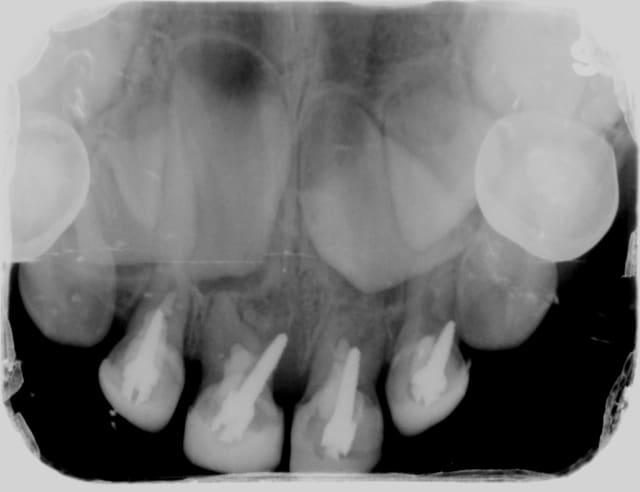

Dans la même journée, j'ai eu une patiente avec une croute de composite posée sur des cavit, exactement comme le 1er message de ce sujet. Le tout bien infiltré comme il faut.

Un autre vient pour pulpite irréversible suite à un amalgame posé à la truelle il y a quelques jours sur une 47 avec effraction pulpaire évidente sur fond de carie de 3 mm (bah oui, si on nettoie trop loin ça fait mal).

Le jeune homme qui vient de sortir a eu des cales occlusales en composite posées par un ortho sur 6 et 7 il y a 4 ans. Ce praticien lui aurait dit en fin de traitement "les cales vont partir seules, pas besoin de les enlever". Aujourd'hui, le jeune homme a gagné le droit d'avoir 3 endo + couronnes et 5 composites sur ses molaires, le tout ajouté à une occlusion catastrophique.

Un autre vient en "urgence" pour un cavit tombé après endo datant d'il y 4 jours par un autre praticien. Ce n'était en fait pas un morceau de cavit tombé mais un pan de dent fracturé car carié. Le praticien a a fait son endo à travers une cavité d'accès remplie de tissu carieux....

Dans le même genre......

Une patiente "basanée" et de surcroit CMU......

Qui se présente aujourd'hui avec de grosses douleurs sur cette 35............

Ca a été fait mi-juin par un de nos confrères bien connus de notre ville, même son assistante sait qu'il fait de la merde.....

En gros, le compo sur 36 (oui il en a fait un !!!) je l'ai fait sauter avec la sonde, et celui sur 35 a sauté tout seul après que je l'ai coupé en 2. Bien évidemment composite qui déborde en interdentaire....

J'ai cureté la carie dessous (qu'on ne pouvait PAS louper à moins d'être aveugle) et évidemment je suis tombé tout droit dans la pulpe......

Moralité : une CC en vue.

Sans parler de la dizaine de petites caries occlusales qu'il n'a pas vu, lui ayant dit que "tout allait bien"....